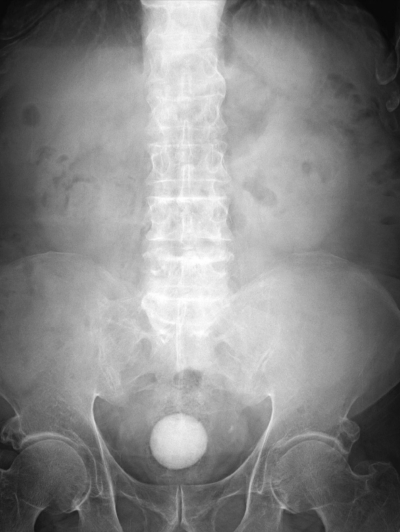

尿所見:蛋白2+、糖(-)、潜血3+、沈渣に赤血球多数/1 視野、白血球多数/1 視野。腹部エックス線写真と腹部CTとを別に示す。尿培養を提出して抗菌薬の投与を開始した。